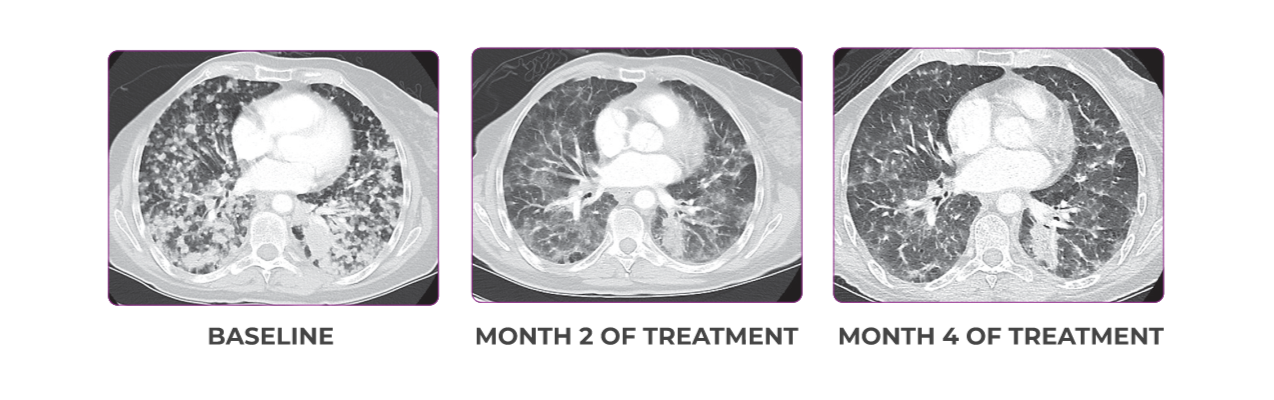

PATIENT CASE:

METASTATIC NSCLC1,a

- 30-year-old female

- Progression on first-line doublet chemotherapy

- PRa after 6 weeks of treatment with VITRAKVI® (larotrectinib)

- Complete clinical response achieved by 12 months with residual scarring

Response to VITRAKVI1

- Partial response and symptom improvement confirmed by chest X-rays after <1 month of treatment

- Imaging performed 6 weeks into treatment revealed considerable decrease in the size of both target lesions

- No treatment-related AEsa were reported

- Patient was symptom free and remained on VITRAKVI

Response in primary and metastatic lesions1

Lung imaging of primary tumors.

SCAN 1: LUNG

SCAN 2: LUNG AND BONE

Images courtesy of Dr Maximilian Hochmair.